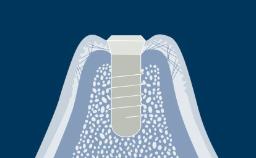

Após a extração dentária, um processo bem descrito de cicatrização ocorre no alvéolo. Uma série de eventos fisiológicos ocorre, resultando em cicatrização de feridas e regeneração óssea dentro do alvéolo. A reabsorção óssea resulta em alterações externas no rebordo alveolar.

O resultado dessa reabsorção é na maioria das vezes uma modificação significativa do contorno pré-extração da crista alveolar, que pode representar um problema para a reconstrução protética posterior. Por esse motivo, o conhecimento do processo de cicatrização após a extração dentária é essencial para o planejamento apropriado do tratamento com implantes sob orientação protética. Este módulo apresentará características anatômicas do osso alveolar e do alvéolo pós-extração e descreverá as alterações histológicas e dimensionais após a extração dentária.